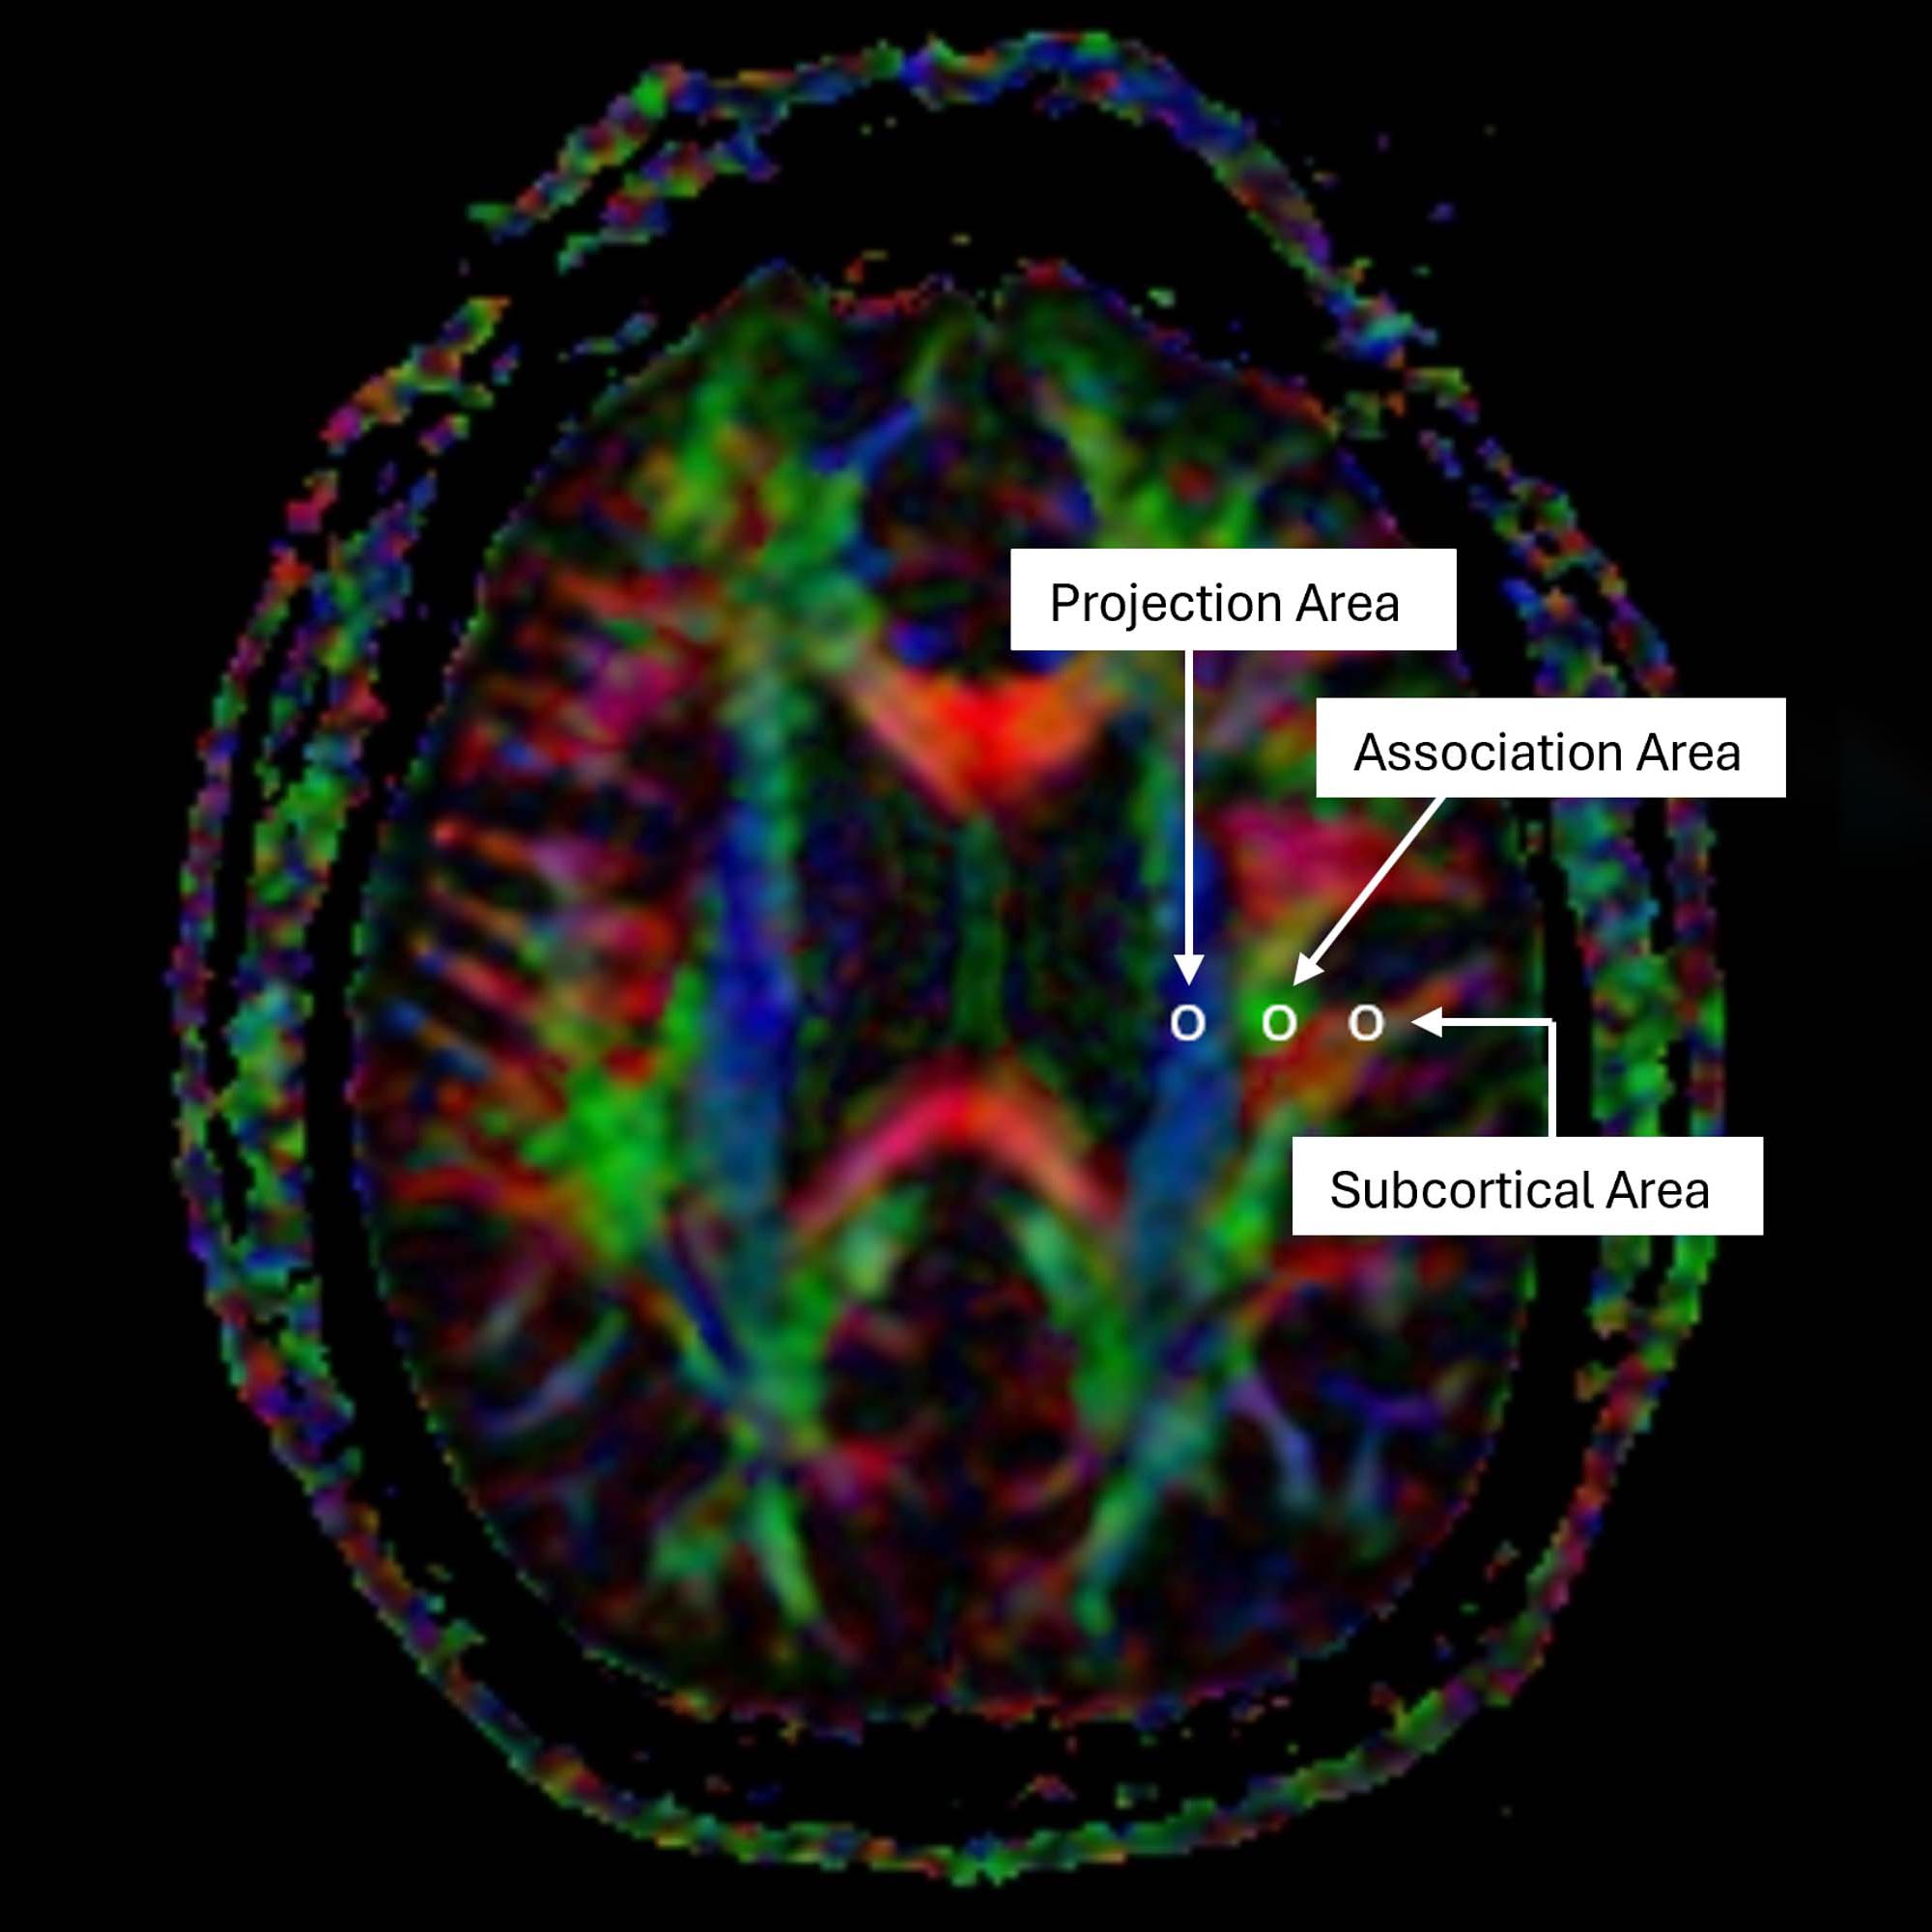

تصوير موتر الانتشار على طول الفضاء المحيط بالأوعية الدموية (DTI-ALPS) هو أسلوب متخصص في التصوير بالرنين المغناطيسي يتتبع كيفية تحرك الماء داخل وحول المساحات المحيطة بقنوات الجهاز الجليمفاوي. تعمل هذه المناطق كمسارات تصريف وتساعد أيضًا في الحفاظ على توازن السوائل وتوصيل العناصر الغذائية والخلايا المناعية وحماية الدماغ من الإصابة.

يوفر مؤشر ALPS المشتق من DTI طريقة غير جراحية لقياس مدى جودة عمل النظام الجليمفاوي. قد يشير انخفاض مؤشر ALPS إلى التدهور المعرفي وقد تم ربطه بتطور الاضطرابات مثل مرض الزهايمر ومرض باركنسون.

تم حساب DTI-ALPS على الرياضيين والضوابط. باستخدام طريقة DTI-ALPS، قام الباحثون بتقييم النشاط الجليمفاوي للرياضيين مع مرور الوقت والعلاقة بين مؤشر ALPS المشتق من DTI وعدد الضربات القاضية التي تعرضوا لها. كما قاموا بقياس الفرق في النشاط الجليمفاوي بين الرياضيين ضعاف الإدراك وغير ضعاف الإدراك.